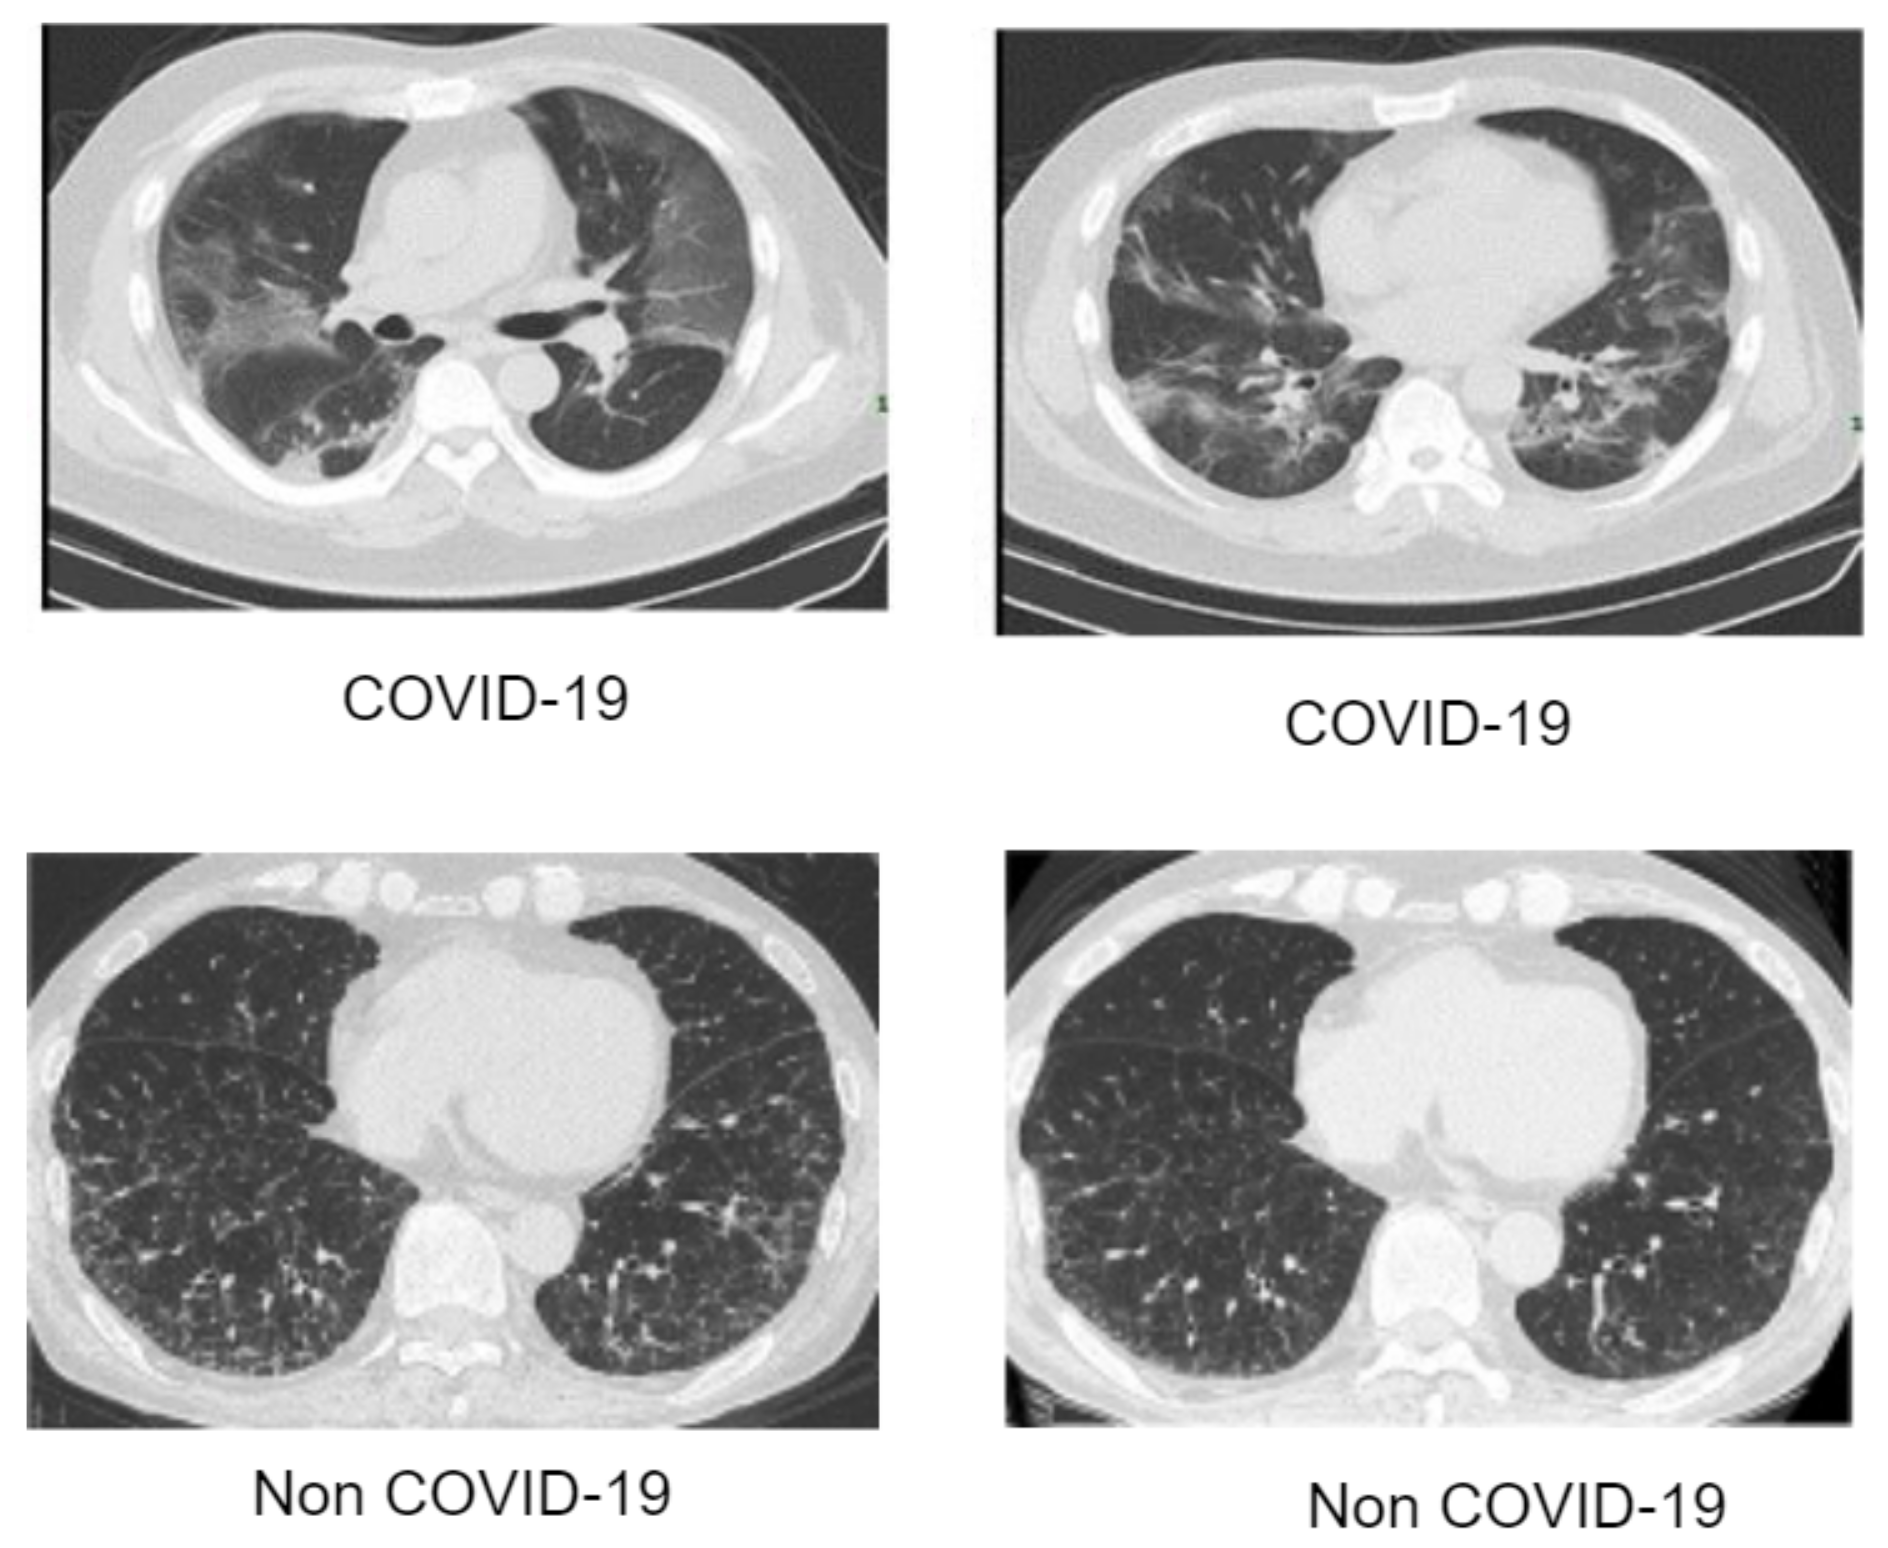

Artificial intelligence (AI) has achieved a remarkable reputation in the field of clinical research. In the face of the current pandemic ravaging our world, AI can assist healthcare workers in the process of disease detection, boosting the accuracy of identification methods at fast rate and perhaps saving lives. The scarcity of appropriate data is perhaps the most significant barrier facing AI-based approaches. Since AI-based approaches are data-driven, a large amount of data is needed. The process of data collection is quite tedious, as there are many ethics concerns from experts. Bearing this view in mind, we resorted to well-known and validated dataset repositories for the collection and compilation of the dataset. In this article, we collected CXR data of different pneumonia related illnesses from three different open sources [45,46,47,48]. As illustrated in Table 1, we collected 3029 scans of bacterial pneumonia, 8851 scans of healthy patients and 2983 scans of viral pneumonia from the Kaggle database of the Radiological Society of North America (RSNA) [45]. We collected 74,999 scans of other pneumonia-related illnesses from National Institute of Health (NIH) [46]. We collected 3616 scans of COVID-19 CXR from the COVID-19 radiography database [47] as illustrated in Table 1 for the purpose of validating our proposed architecture for multiple classification problems. The COVID-19 CT samples were obtained from COVID-19 dataset [48] as depicted in Table 2 for binary classification. As indicated, there are approximately 93,627 CXR scans including COVID-19 and 10 other pneumonia-related illnesses as well as healthy instances and a total of 2482 CT scans of COVID-19 and non-COVID-19 samples. Since the number of each category of data class varies, as a result, we selected 2000 scans of CXR from each category which sum up to 24,000 CXR images. Since the amount of CXR associated with each class is balanced, the dataset is partitioned into three sets of 70%, 20%, and 10% for training, validation, and test, respectively. Similarly, the CT dataset is also partitioned in the same manner from a selection of 1230 scans from each category. Figure 1 gives a visual representation of the dataset distribution for CXR scans while Figure 2 displays the visual representation for the CT scans.

Figure 2. Data collection of computed tomography (CT) images of COVID-19 and non-COVID-19.